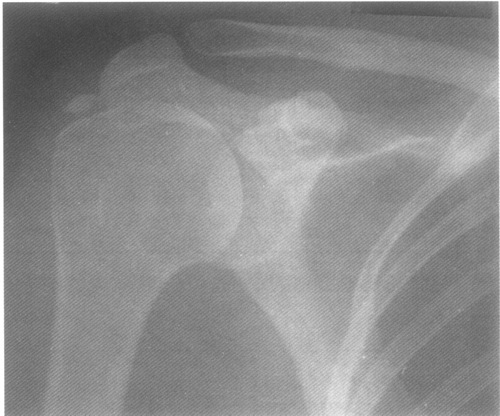

Рентгеновские снимки остеосклероза костной ткани